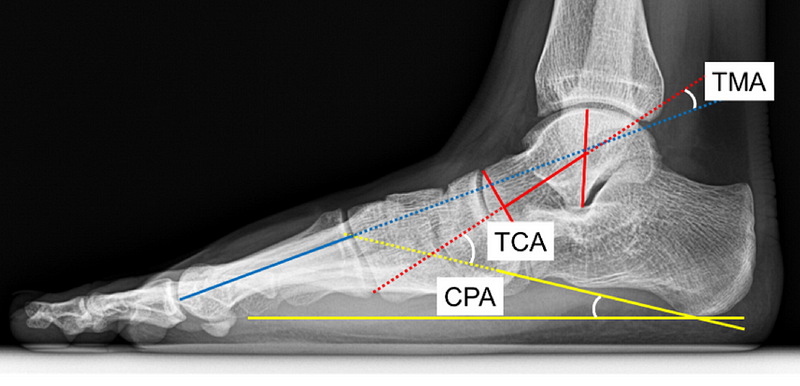

정형외과의 병역판정은 앞서 서술한 대로 각도, 길이, 면적 측정 등으로 이루어지는 부분이 많습니다. 예를 들면, 제가 근무할 당시에는 척추측만증의 경우 Cobb의 각도가 20도 이상이면 4급 보충역, 40도 이상이면 5급 전시근로역으로 판정했습니다. 또한 평발의 경우에는 거골-제1중족골 각도가 16도 이상, 또는 종골경사각이 10도 미만이면 4급 보충역으로 판정했습니다. (사진 1) 물론 현재는 기준이 달라졌습니다.

1*XaP1OL0OlGDxNbqAIhYlTA.png 사진 1. 평발 판정을 좌우하는 X-ray 각도 측정. 미세한 수치 차이가 한 사람의 군 복무 운명을 결정합니다. (Ryu et al., Eur Radiol 33, 2023)